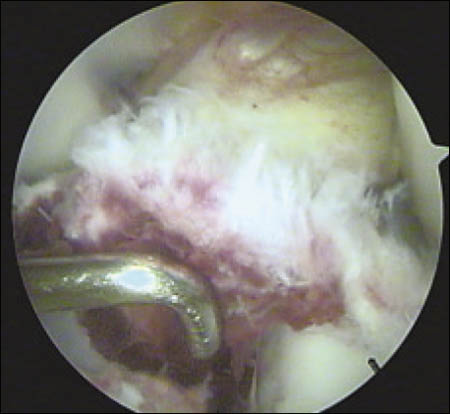

Se realiza un mini abordaje anterior de rodilla 2 cm proximal al polo inferior de la rótula y 3 cm distal al mismo, luego se realiza la esqueletización del polo patelar distal cruentándolo a la demanda. Mediante dicho gesto se reconoce la superficie ósea permitiendo la implantación precisa de los arpones, centralizándolos en plena masa esquelética, se colocan en forma paralela 2 anclajes óseos de 3.5 mm (Arthrex). (Fig. 3 y 4)

Figura 3: Visión intraoperatoria de la lesión del tendón patelar, colocación de 2 arpones paralelos

Figura 4: Maniobra de tracción de las hebras de sutura Fiber-wire en sentido distal, arpones firmemente fijados.